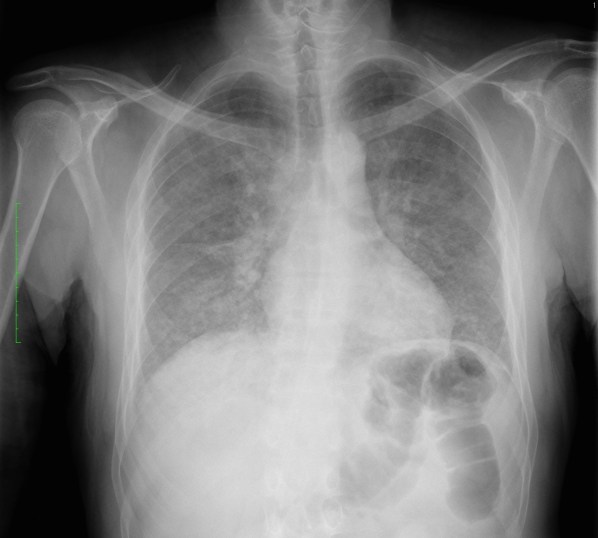

Solución: Es un estudio Normal. Silueta cardiomediastínica y parénquimas pulmonares sin alteraciones significativas.

CASO: sospecha de neumonía.

Hallazgos:

- En un principio podríamos decir que existe un aumento de densidad retrocardiaco que podría ser compatible con condensación neumónica a dicho nivel, sin embargo estamos ante una placa poco inspirada, lo cual puede llevarnos a cometer errores diagnósticos.

- Se recomendó volver a realizar la radiografía, observar a continuación:

Ya no se observa el aumento de densidad retrocardiaco, la placa es normal.

INSPIRACIÓN: Una placa bien inspirada es aquella en la que se observar 6-7 arcos costales anteriores o 10-11 arcos costales posteriores. Lo contrario puede producir imágenes falsas de condensaciones o de seudocardiomegalia.